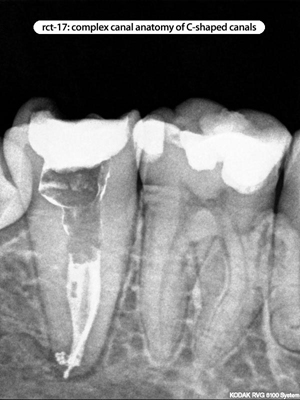

Root Canal Cases